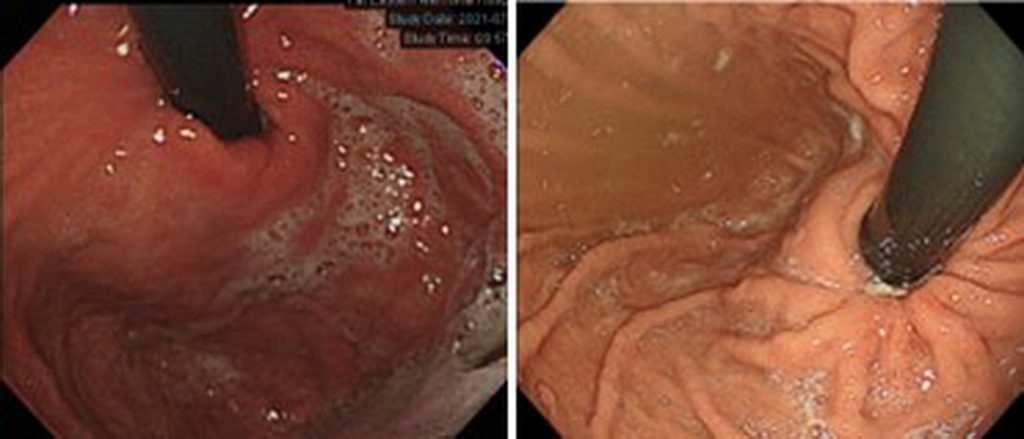

長期受到胃酸逆流和胸口灼熱困擾的54歲賴姓男子,由於飲食時間不規律,且經常參與社交應酬,致長期服用藥物控制卻效果有限;經到板橋亞東醫院採用經口胃鏡進行電燒灼術,以處理鬆弛的胃賁門黏膜,燒灼後形成潰瘍結疤使胃賁門緊縮,從而減少胃內物質逆流到食道,手術後讓賴男減少對藥物的依賴,無需每日服藥。

在臨床上,常有患者因依賴藥物而產生副作用,或長期使用後效果逐漸降低的情況。鍾承軒表示,過去對於持續服藥但症狀未見改善的患者,常以外科胃底摺疊手術重建胃食道交界的障蔽功能,惟近年隨著消化道內視鏡技術進步,提供無需開刀的新型治療方式「經口胃鏡微創抗逆流」。